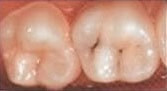

Eine Fissurenversiegelung der Zähne ist eine wirksame Methode, um Zähne vor Karies zu schützen. Dabei sind manche Zähne anfälliger als andere. Backenzähne sind insbesondere aufgrund ihrer großen Kaufläche und Position anfälliger von Karies angegriffen zu werden als Schneidezähne. Denn auch die Reinigung der Zahnoberfläche wie der Außenwände ist durch die Stellung meist komplizierter.

Zunächst einmal werden die Zähne auf ihren Zustand geprüft. Denn nur gesunde Zähne werden versiegelt. Anschließend werden die Zähne gereinigt. Dabei wird hartnäckiger Zahnbelag bzw. Zahnstein abgetragen. Sind die Zähne von Plaque befreit, werden sie getrocknet, damit der Kunststoff besser haften kann. Um die Zähne leicht anzurauen, verwendet nun der Zahnarzt eine spezielle Säure. Zum Schluss werden die Kauflächen, Rillen und Furchen der Zähne mit einer dünnen Schicht aus Kunststoff oder Glasionomerzement überzogen und mit einer speziellen Lampe ausgehärtet. Dadurch werden die für Karies besonders anfälligen Fissuren verschlossen.

Versiegelter Zahn